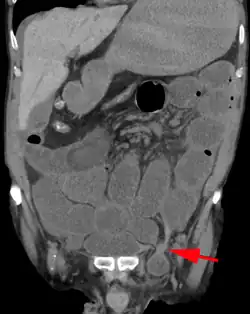

An incarcerated inguinal hernia as seen on cross sectional CT scan

A frontal view of an incarcerated inguinal hernia (on the patient's left side) with dilated loops of bowel above.

An inguinal hernia which contains part of the bladder. Bladder cancer is also present.

When assessed by ultrasound or cross sectional imaging with CT or MRI, the major differential in diagnosing indirect inguinal hernias is differentiation from spermatic cord lipomas, as both can contain only fat and extend along the inguinal canal into the scrotum.[22]

On axial CT, lipomas originate inferior or lateral to the cord, and are located inside the cremaster muscle, while inguinal hernias lie anteromedial to the cord and are not intramuscular. Large lipomas may appear nearly indistinguishable as the fat engulfs anatomic boundaries, but they do not change position with coughing or straining.[22]